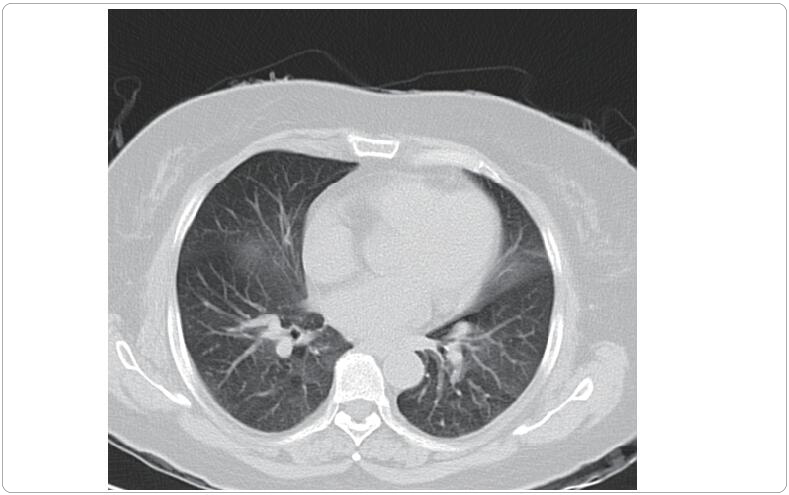

The CT scan shows pulmonary consolidation and inflammatory hyperplasia, which is considered to be a crucial mortality risk factor in Stevens–Johnson syndrome and toxic epidermal necrolysis. (Courtesy of Dr. Jinhua Xu. See pages 585-593 by Yanhong Shou et al. for more information.)